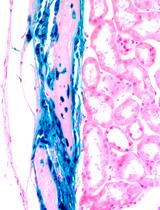

Liver fibrosis results from the excessive collagen deposition (collagen scar) by activated hepatic stellate cells (HpSCs), leading to the inhibition of normal liver regeneration and function. Fibrogenesis is a complex mechanism involving both the synthesis and degradation of matrix proteins by different cell types, mainly macrophages in the liver. Carbon tetrachloride-induced fibrosis (CCl4) and cirrhosis is one of the oldest, simplest and probably the most widely used toxin-based experimental model for the induction of fibrosis. Here we have explained experimental animal model of liver fibrosis using CCl4, injecting twice a week for a period of 8 weeks. In these fibrotic mice, bone marrow (BM) derived CD45+ cells were transplanted via intrasplenic route after 8 weeks of CCl4 injection, and half of the CCl4 dose was continued till the end of the experiment to know the effect of transplanted cells on liver fibrosis and regeneration. So far, crude bone marrow (BM) cells or mesenchymal stem cells (MSCs) have been used for the treatment of liver fibrosis. Low survival rate, less fibrolytic and profibrogenic properties of MSCs remain the major concerns for inadequate recovery of liver from fibrosis. This led us to investigate BM cells devoid of mesenchymal lineage that is CD45+ cells for the antifibrotic effect as this population consisting of mononuclear cells which are the precursor of macrophages and may involve in the scar degradation process. Cells transplantation can be followed in different ways like intrasplenic infusion, tail vein injection and ectopic cell transplantation in experimental animal models. The survival of the cells after ectopic transplantation is less when compared to tail vein and intrasplenic infusion. Intrasplenic route of transplantation is effective in engraftment and long term survival of the donor cells especially in case of liver disease models. This protocol describes fibrosis mouse model development, intrasplenic route of cell transplantation and tracking of the donor cells after transplantation.